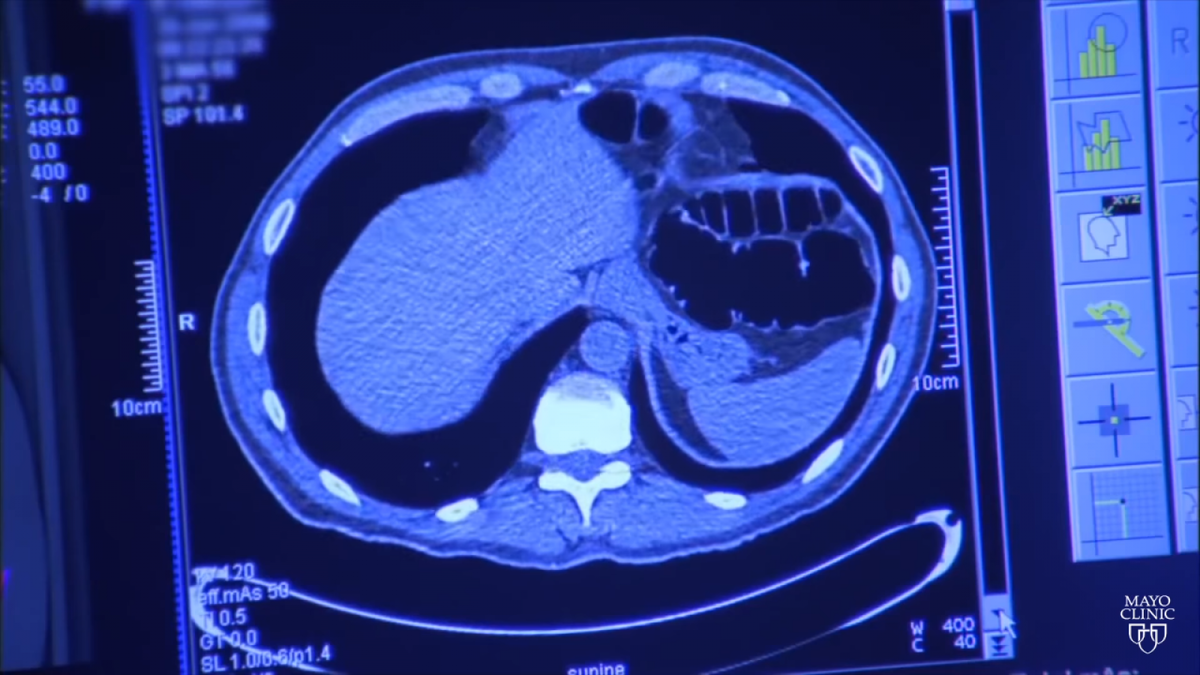

Разработчики Google, сотрудничающие с Медицинской школой Северо-Восточного университета в США, создали модель искусственного интеллекта (artificial intelligence, AI), способную выявлять рак легких на основе скрининговых тестов лучше, чем радиологи-люди со средним восьмилетним опытом работы.

При анализе результатов по одному скану компьютерной томографии (КТ) модель выявляла рак в среднем на 5% чаще, чем группа из шести экспертов и на 11% реже давала ложноположительные результаты. Люди и искусственный интеллект достигли аналогичных результатов, когда радиологи смогли просмотреть результаты предыдущего КТ-сканирования.

Когда дело доходило до прогнозирования риска развития рака через два года после скрининга, модель смогла обнаружить рак на 9,5% чаще, по сравнению с радиологами.

Подробно описанная в исследовании, опубликованном в журнале Nature Medicine, модель на базе алгоритма глубокого обучения использовалась для прогнозирования наличия у пациента рака легких, генерируя для него оценку риска развития рака легких и определяя местоположение злокачественных новообразований в лёгких.

Модель была разработана с использованием более чем 42 000 скрининговых изображений КТ грудной клетки, полученных от примерно 15 000 пациентов, 578 из которых заболели раком в течение года, в ходе исследования, проведенного в 2002 году Национальным институтом здравоохранения США.